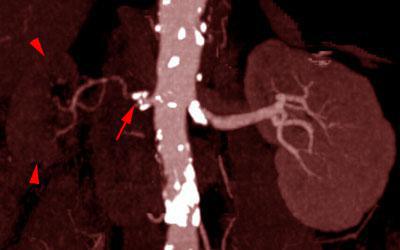

Estenosis intensa de arteria renal 1